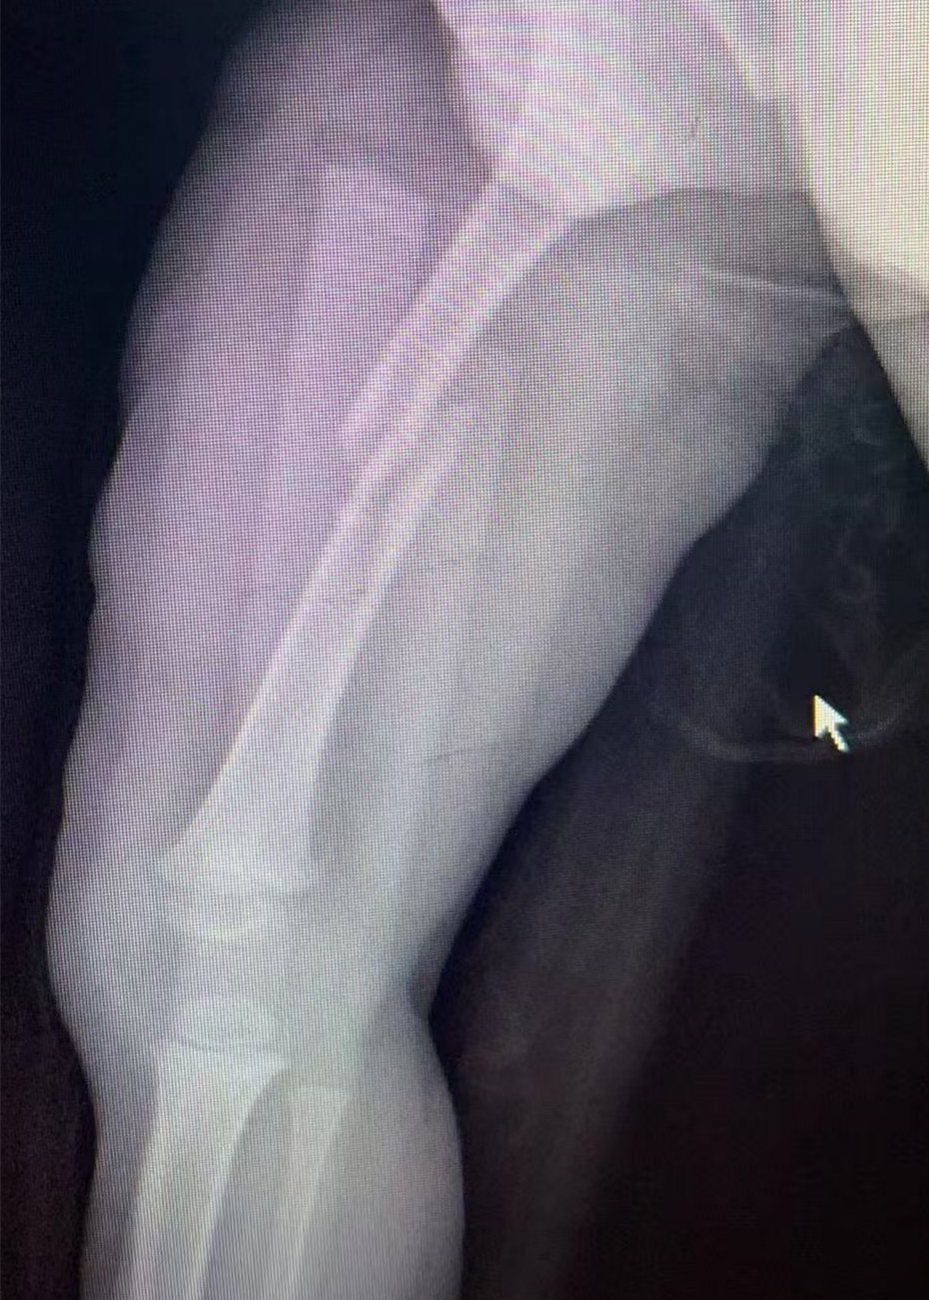

儿童尺桡骨双骨折闭合复位微创弹性髓内针内固定

图片图片图片

儿童股骨干骨折闭合复位微创弹性髓内针内固定